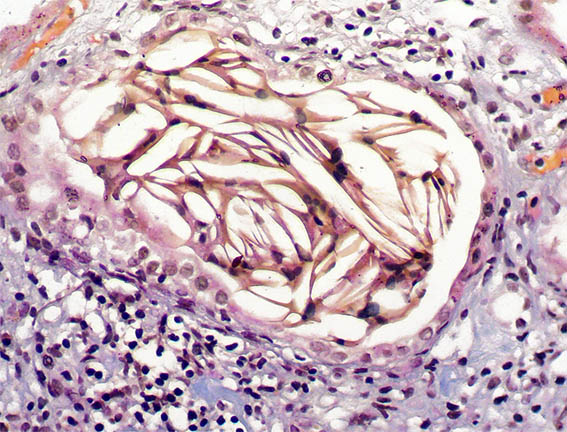

Figura 6. Plata-metenamina, X200.

Figura 7. H&E, X200.